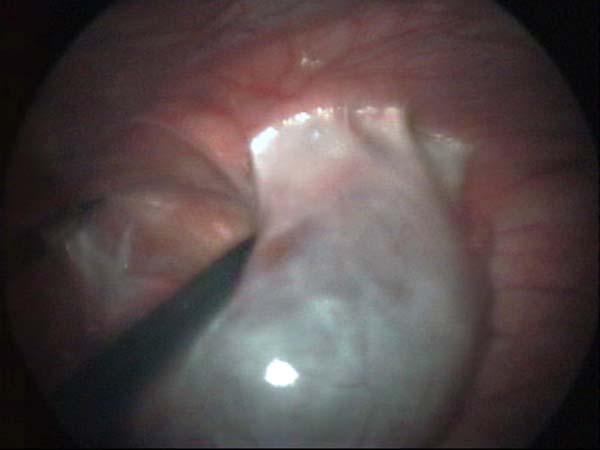

Photos laparoscopie Kyste ovarien Cystectomie ovarienne Septum utérin Grossesse tubaire